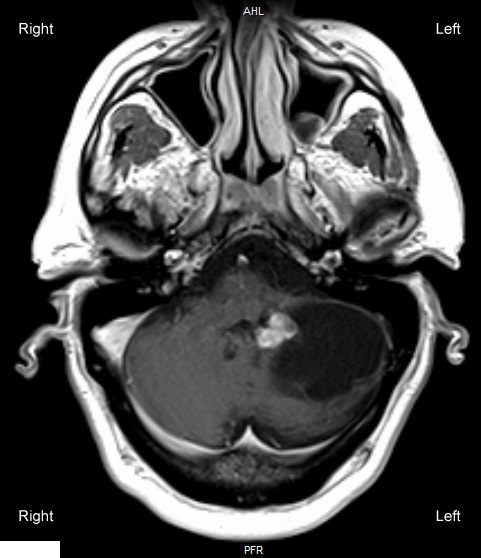

A 55-year-old man arrives at the office complaining of headaches that have worsened during the last two months. The throbbing headaches are commonly accompanied by nausea and increase anytime the patient coughs or bears down during a bowel movement. For episodic migraine without aura, medical history is important. A cystic mass is shown by gadolinium MRI of the brain, as demonstrated in the figure below: A 55-year-old man arrives at the office complaining of headaches that have worsened during the last two months. The throbbing headaches are commonly accompanied by nausea and increase anytime the patient coughs or bears down during a bowel movement. For episodic migraine without aura, medical history is important. A cystic mass is shown by gadolinium MRI of the brain, as demonstrated in the figure below:   Which of the following findings is most likely to be seen on physical examination of this patient? A) Left dysdiadochokinesia B) Left Horner syndrome C) Left oculomotor nerve palsy D) Photophobia E) Right hemiparesis F) Right hemisensory loss G) Right homonymous hemianopia H) Right lower facial droop Which of the following findings is most likely to be seen on physical examination of this patient?